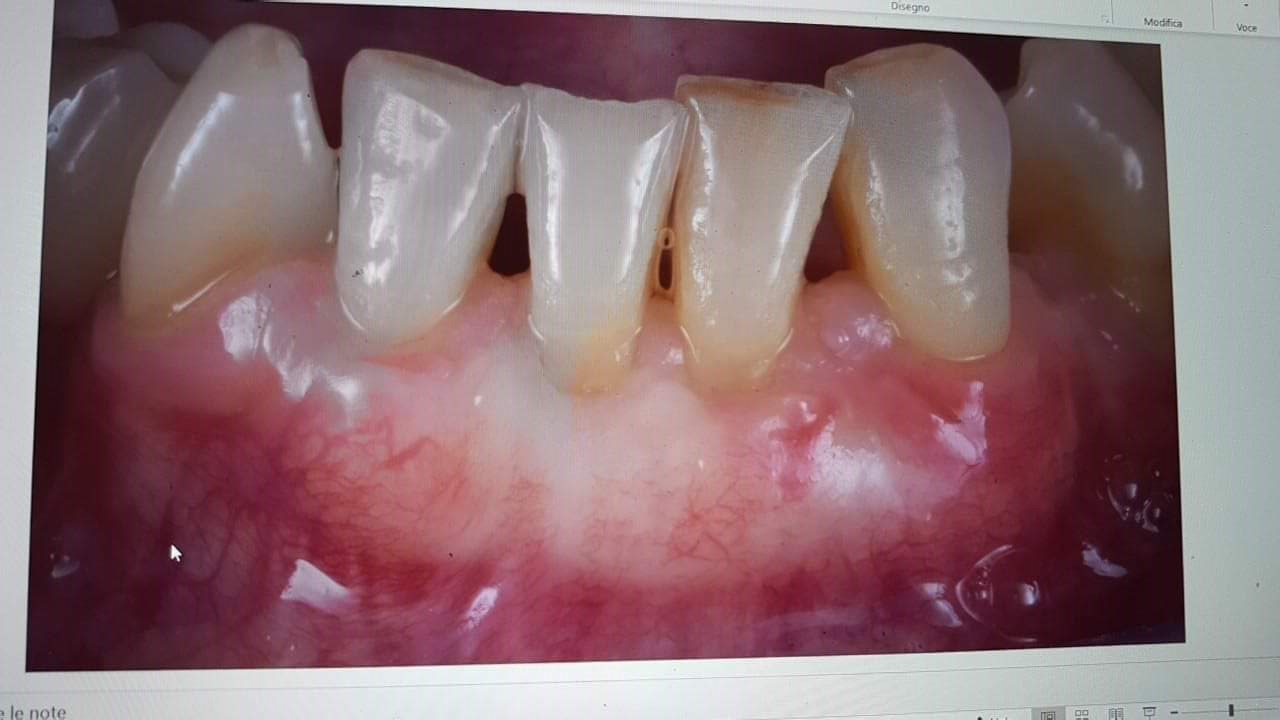

E il follow up a 2 anni che mi hanno chiesto (sorry foto dello schermo fatta con il cellulare ?)